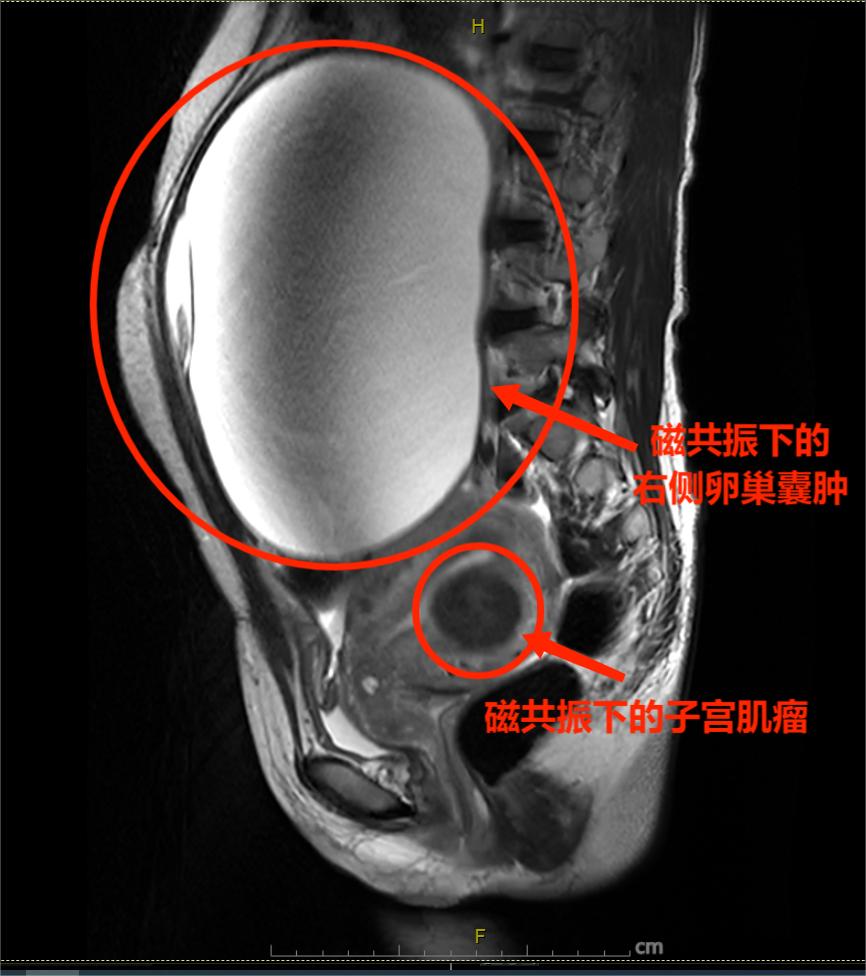

考虑到李女士本身患有中度贫血,另外实施手术的范围比较大,在与李女士进行充分沟通后,武汉市普仁医院妇科医疗团队在术前为李女士给予了输血治疗,同时制定了完善的手术方案,并于7月11日上午为李女士实施了手术。术中可见其子宫左前壁有一约一元人民币大小肌瘤,而右侧卵巢囊肿则约足球大小,左侧卵巢囊肿约鸡蛋大小,武汉市普仁医院妇科医疗团队当即将病灶全部摘除,整个手术进行的十分顺利,全程耗时75分钟,术中出血不足50ml。

磁共振下的右侧卵巢囊肿

“她囊肿里的囊液足足有2900ml,和囊袋加起来将近有7斤重,如果再不治疗,囊肿不仅会继续变大进一步压迫到其他脏器,更会压迫胸腔导致呼吸困难,其次,她的中度贫血也是因为子宫肌瘤导致月经增多引起的,切除后对其贫血也会有较大的改善,”妇科陈赛兰医生介绍。